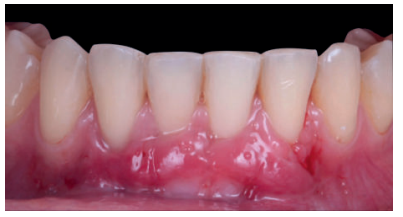

El control a la semana (Figura 13) presentaba inflamación moderada y a las 2 semanas (Figura 14) se retiraron los puntos de sutura. La paciente acudió a los 4 meses (Figura 15) y al año (Figura 16) a visitas de revisión, donde se apreció una buena banda de tejido queratinizado y una pequeña cicatriz.

Los presentes casos clínicos demuestran que la técnica de Edlan-Mejchar modificada (vestibuloplastia + ITC) es eficaz para el tratamiento de recesiones gingivales unitarias y múltiples con 1 mm o menos de tejido queratinizado apical en el sector anteroinferior, presentando estabilidad después de 18 meses.

Una limitación de la técnica quirúrgica es la formación de una pequeña cicatriz en el fondo del vestíbulo. Bethaz y cols.19 encuentran, tras la maduración de los tejidos, la formación de una pequeña cicatriz en 5 de los 7 casos (71.4%). Se puede observar la formación de una pequeña cicatriz en el segundo caso clínico presentado, no existiendo formación de dicha cicatriz en el primer caso clínico.